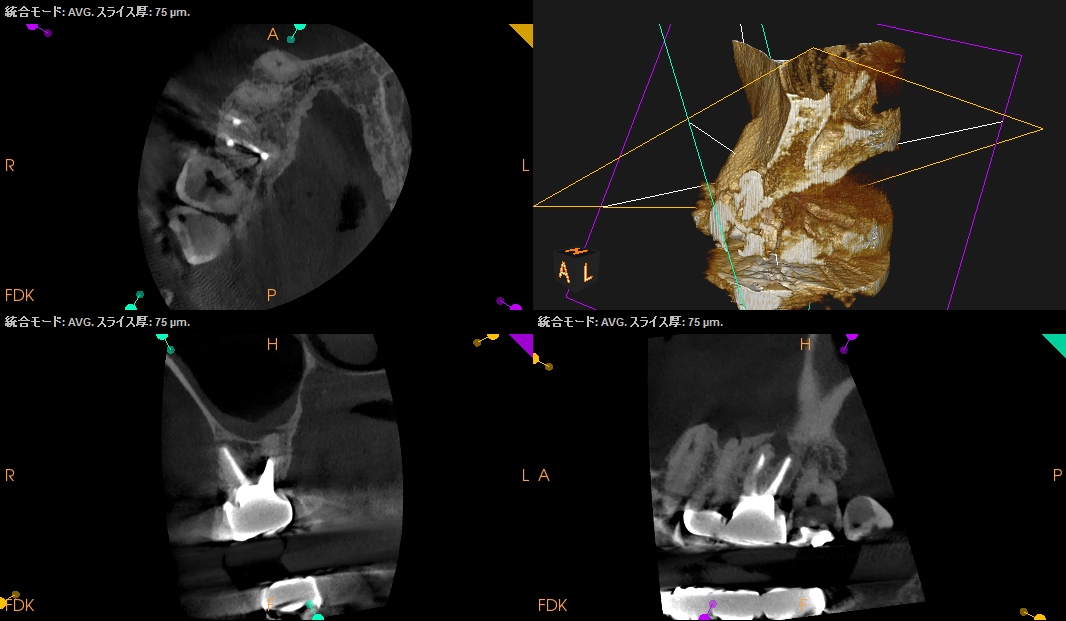

Pre-op Endo test(2025.2.18)

#3

MB

DB

P

治療前の予測としては以下だ。

CEJよりも13mm先にApexがある。

が、この際にOsteotomyを行わなくてもApexには辿り着ける。

そしてApexから3mmで切断した時に、頬舌的には4.4mm削るだけで済む。

Very easyな外科治療だ。

そしてその際、Gutta PerchaがMBの中心にあることからこの根管は1根管であるということまでわかる。

まさにSuper easyなApicoectomyである。

このように

見れる・わかる・映りがいいCarestream社のようなCBCTがあれば, ここまで術前に予測ができるのである。